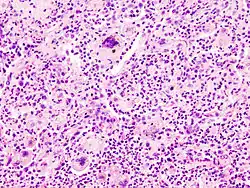

| Microscopic image of aspiration pneumonia in an elderly person with a neurologic illness. Note foreign-body giant cell reaction. | |